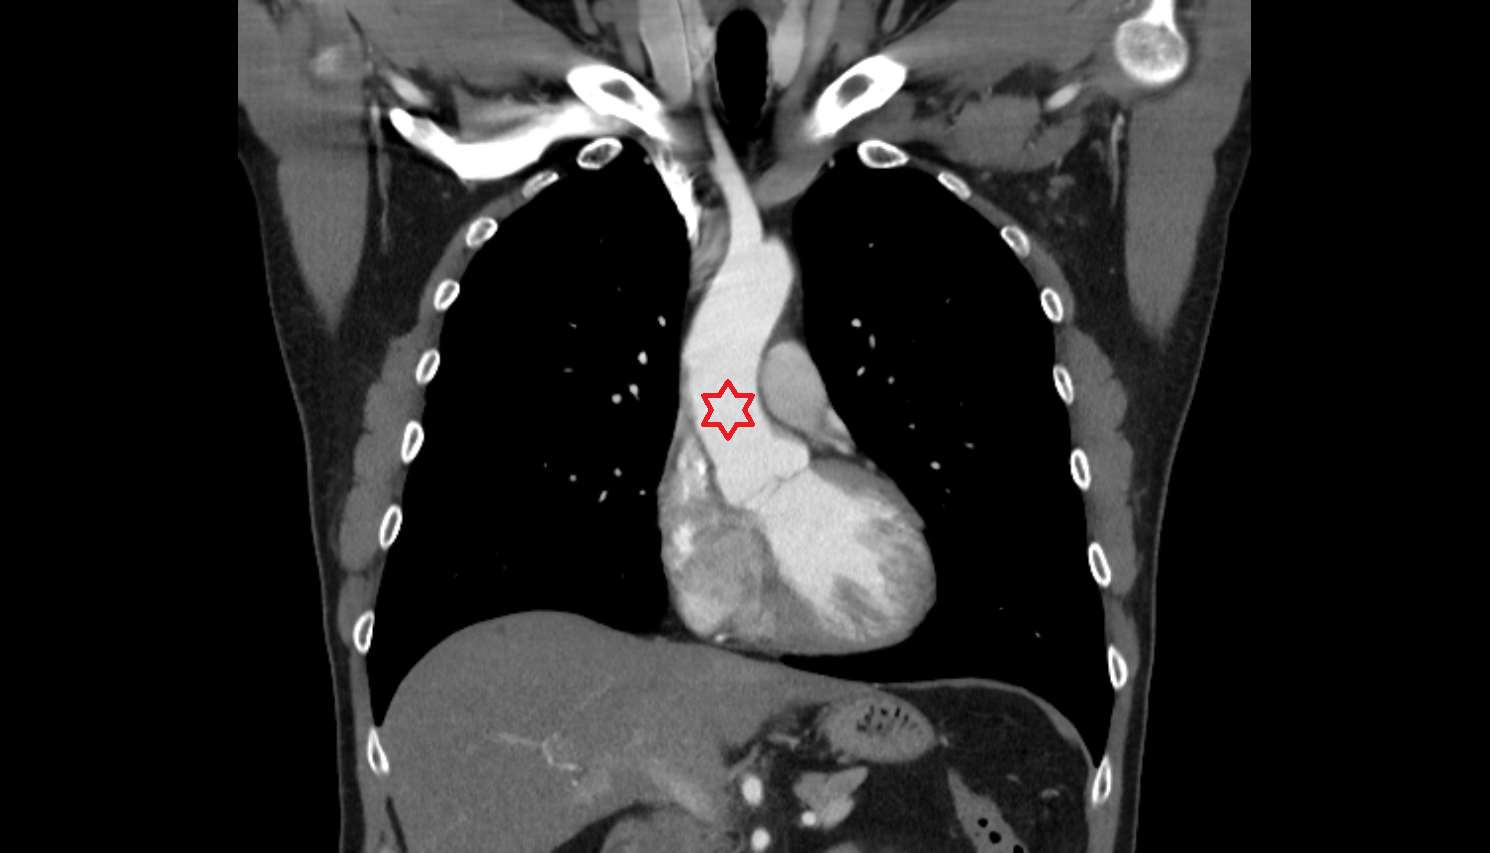

- Pericardium

- Heart

- Ascending aorta

- Arch of aorta

- Descending thoracic aorta

- Superior vena cava